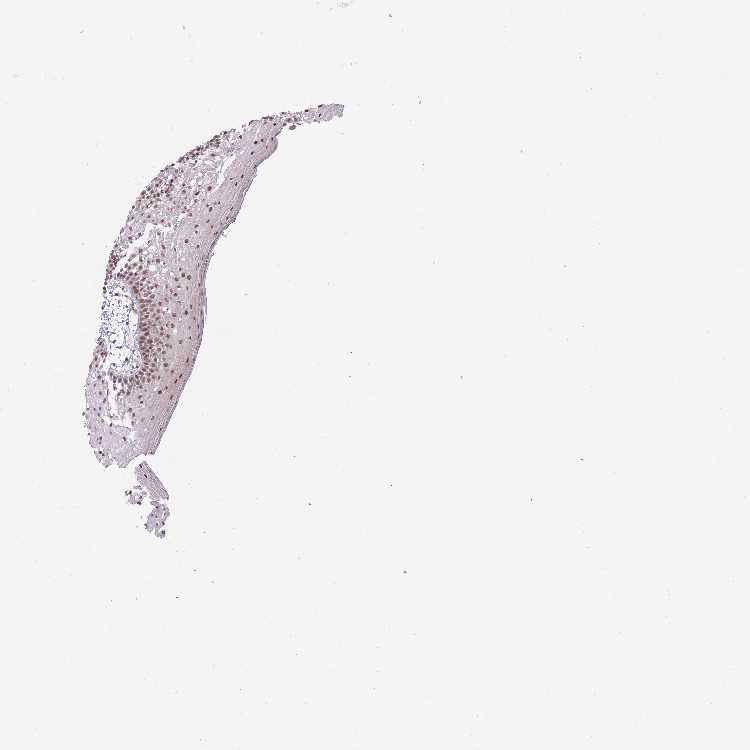

TISSUE PRIMARY DATA ORAL MUCOSA Show tissue menu

ORAL MUCOSA - Antibody stainingi

Antibody staining in the annotated cell types in the current human tissue is reported as not detected, low, medium, or high, based on conventional immunohistochemistry profiling in selected tissues. This score is based on the combination of the staining intensity and fraction of stained cells.

Each image is clickable and will lead to virtual microscopy that enables deeper exploration of all samples and also displays staining intensity scores, fraction scores and subcellular localization as well as patient and tissue information for each sample.

Antibody HPA046290Antibody HPA049475Antibody CAB046477

Squamous epithelial cells HighMediumHigh